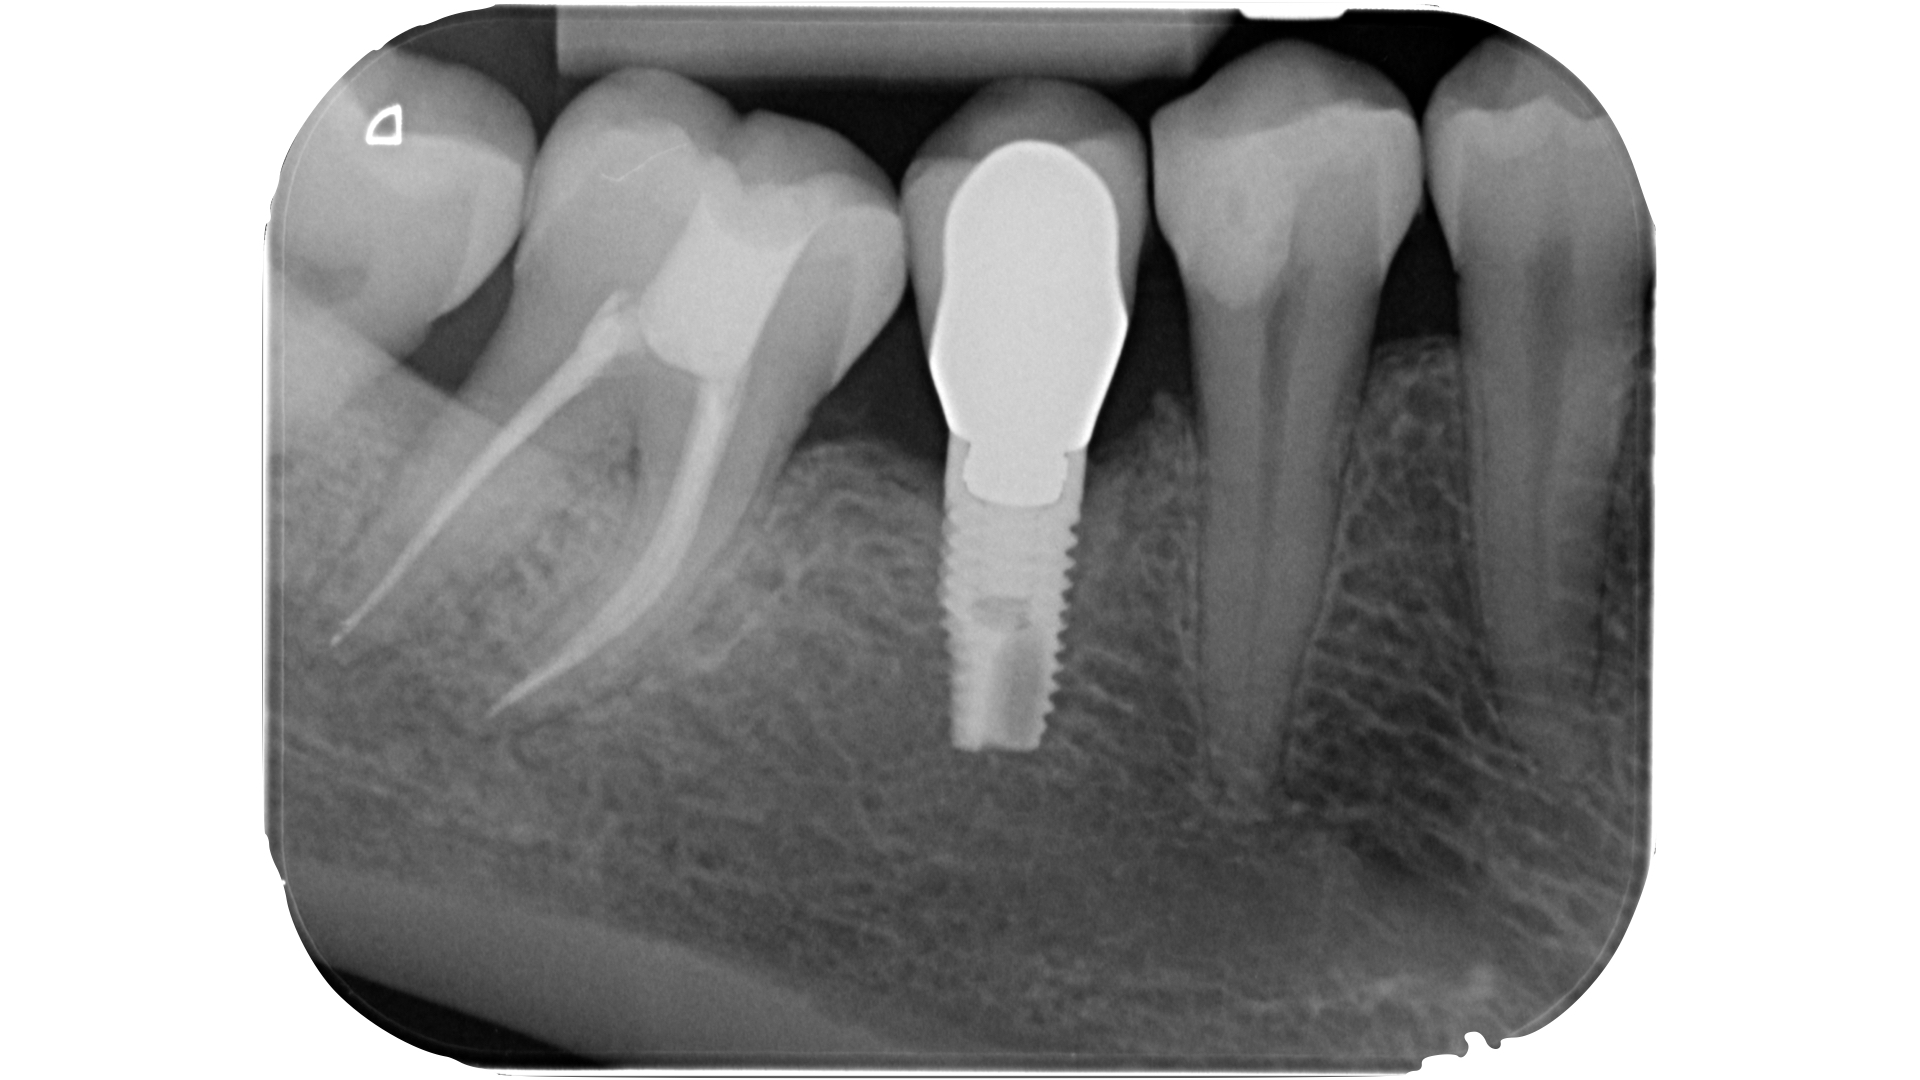

Nei molari la distanza tra la sommità di qualsiasi cuspide e il tetto della camera pulpare è di circa 6,3 mm, nei premolari superiori è di 6,94 mm.

La camera pulpare ha un’altezza di circa 1,5-2 mm e la distanza media dal pavimento della camera alla forca è di 3 mm circa (Tabella 1) (Figura 13).

La fresa che ci guida in questo step ha una parte lavorante di 6 mm (Komet 880-314-012) che, ricordando una delle regole di Deutsch, non dovrà penetrare oltre il nostro punto di repere occlusale: diventerebbe alto il rischio di sovra estendere la preparazione e di indebolire se non di perforare il pavimento (Figura 14).

La parte diamantata della fresa è la nostra guida, lo stop oltre il quale è sconsigliato procedere nei molari superiori e inferiori.